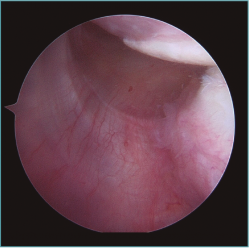

Figura 1. Visión desde portal lateral del hombro derecho. Paciente de 18 años con cuadro de inestabilidad de hombro recidivante. Se visualiza una gran laxitud articular con una lesión labral mínima.